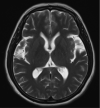

We reported a case of a 48-year-old female patient admitted to the hospital due to balance disorder which progressed rapidly within 1 week. Cerebral magnetic resonance imaging showed significant atrophy and hyperintensities at the middle cerebellar peduncles and the "hot cross bun" sign of the pons. The final diagnosis was probable multiple system atrophy, cerebellar subtype. The clinical and imaging findings will be discussed as well as a brief literature review.